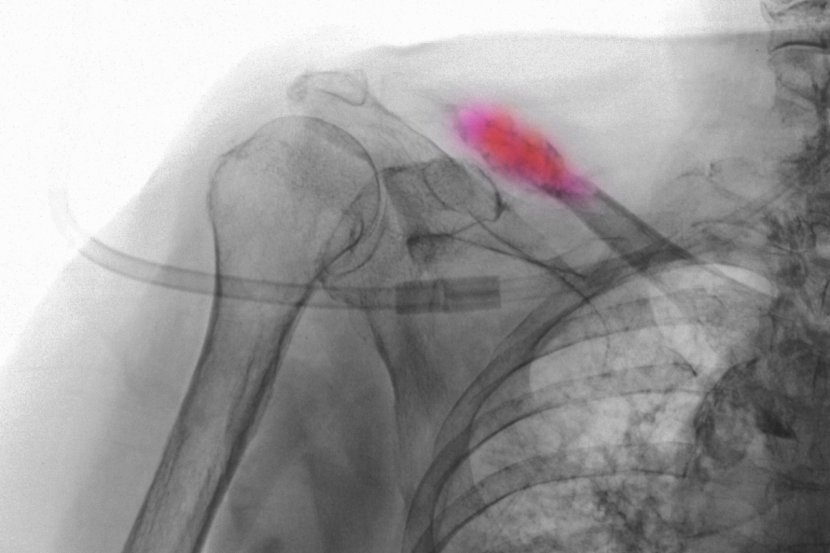

Rak može da se proširi na bilo koju kost u telu, ali, najčešća mesta na kojima se metastaze prvo javlajju su:

• kičma (pršljenovi)

• rebra

• karlica (kost kuka)

• grudna kost

• lobanja.

Najčešći simptom metastaza na kostima, i obično prvi koji se javlja, je bol u kosti. Bol u kostima može da se javi i nestane, ili može da bude konstantan. Često je bol mnogo jači noću nego danju i može da se javi samo u jednoj oblasti ili da se proširi po celom telu. To može da bude tup ili oštar bol, a uz bol može da se javi i otok. Ostali simptomi metastaza na kostima su slomljene kosti (prelomi), najčešće rebara, pršljenova i dugih kostiju nogu.